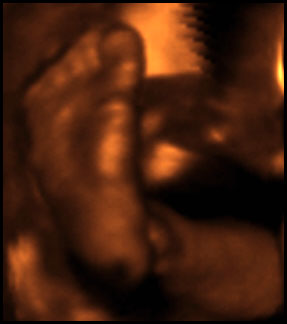

Anyway, here he is....toes and all.

You guys. That's my SON in there! My god, I can't wait to meet him.